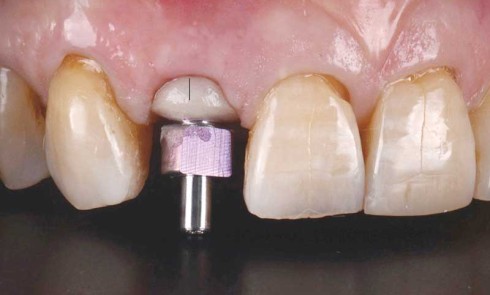

Article réservé à nos abonnés CAD CAM et pilier implantaire : la gestion du profil d’émergence

Le défi en implantologie est de répondre aux attentes esthétiques des patients dans les cas de restaurations antérieures. Le volume...